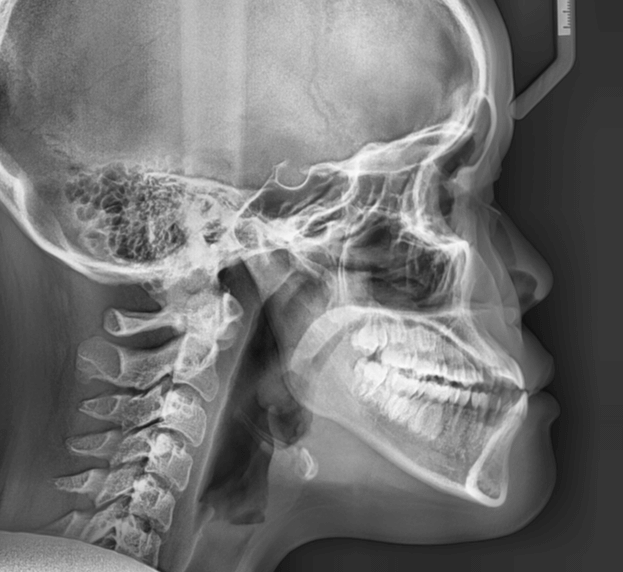

咬み合わせが逆であること(反対咬合)が気になる

| 年齢・性別 | 15歳 女性 |

|---|---|

| 主訴 | 咬み合わせが逆であること(反対咬合)を気にされて来院された女性。見た目や機能面の改善を希望されていました。 |

| 治療期間・回数 | 4年4ヶ月・28回 |

| 費用 | 900,000円 |